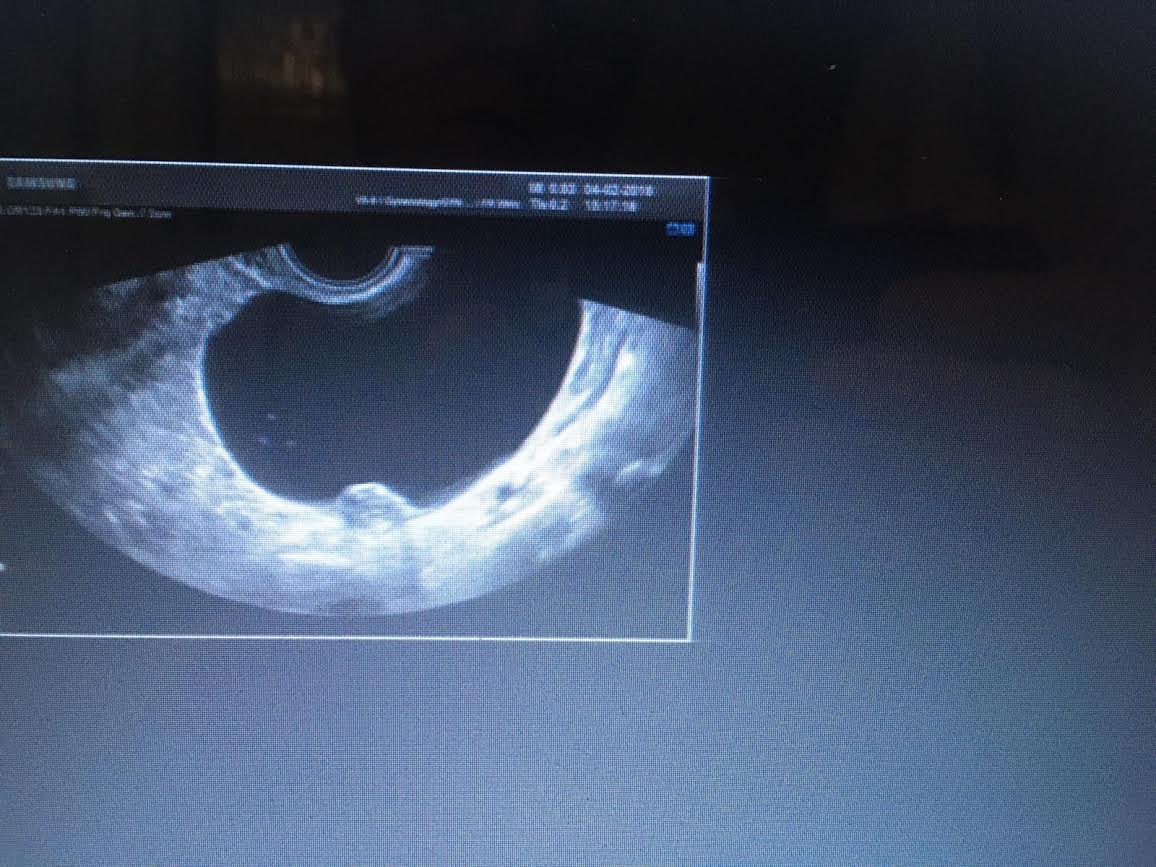

Immagine ecografica di DILATAZIONE  dei VENTRICOLI CEREBRALI LATERALI (Ventricolomegalia)